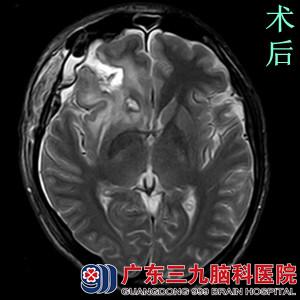

完善相关检查后,由鲁明主任主刀,在全麻下行右侧额叶海绵状血管瘤切除术+血肿清除术。术中导航定位右侧额叶病变,显微镜下见血肿,予吸引器吸出凝血块,见右侧额叶内侧病变,予显微镜下全切除,手术顺利结束。术后经过专科治疗护理,两周后康复出院。术后病理结果:海绵状血管瘤。